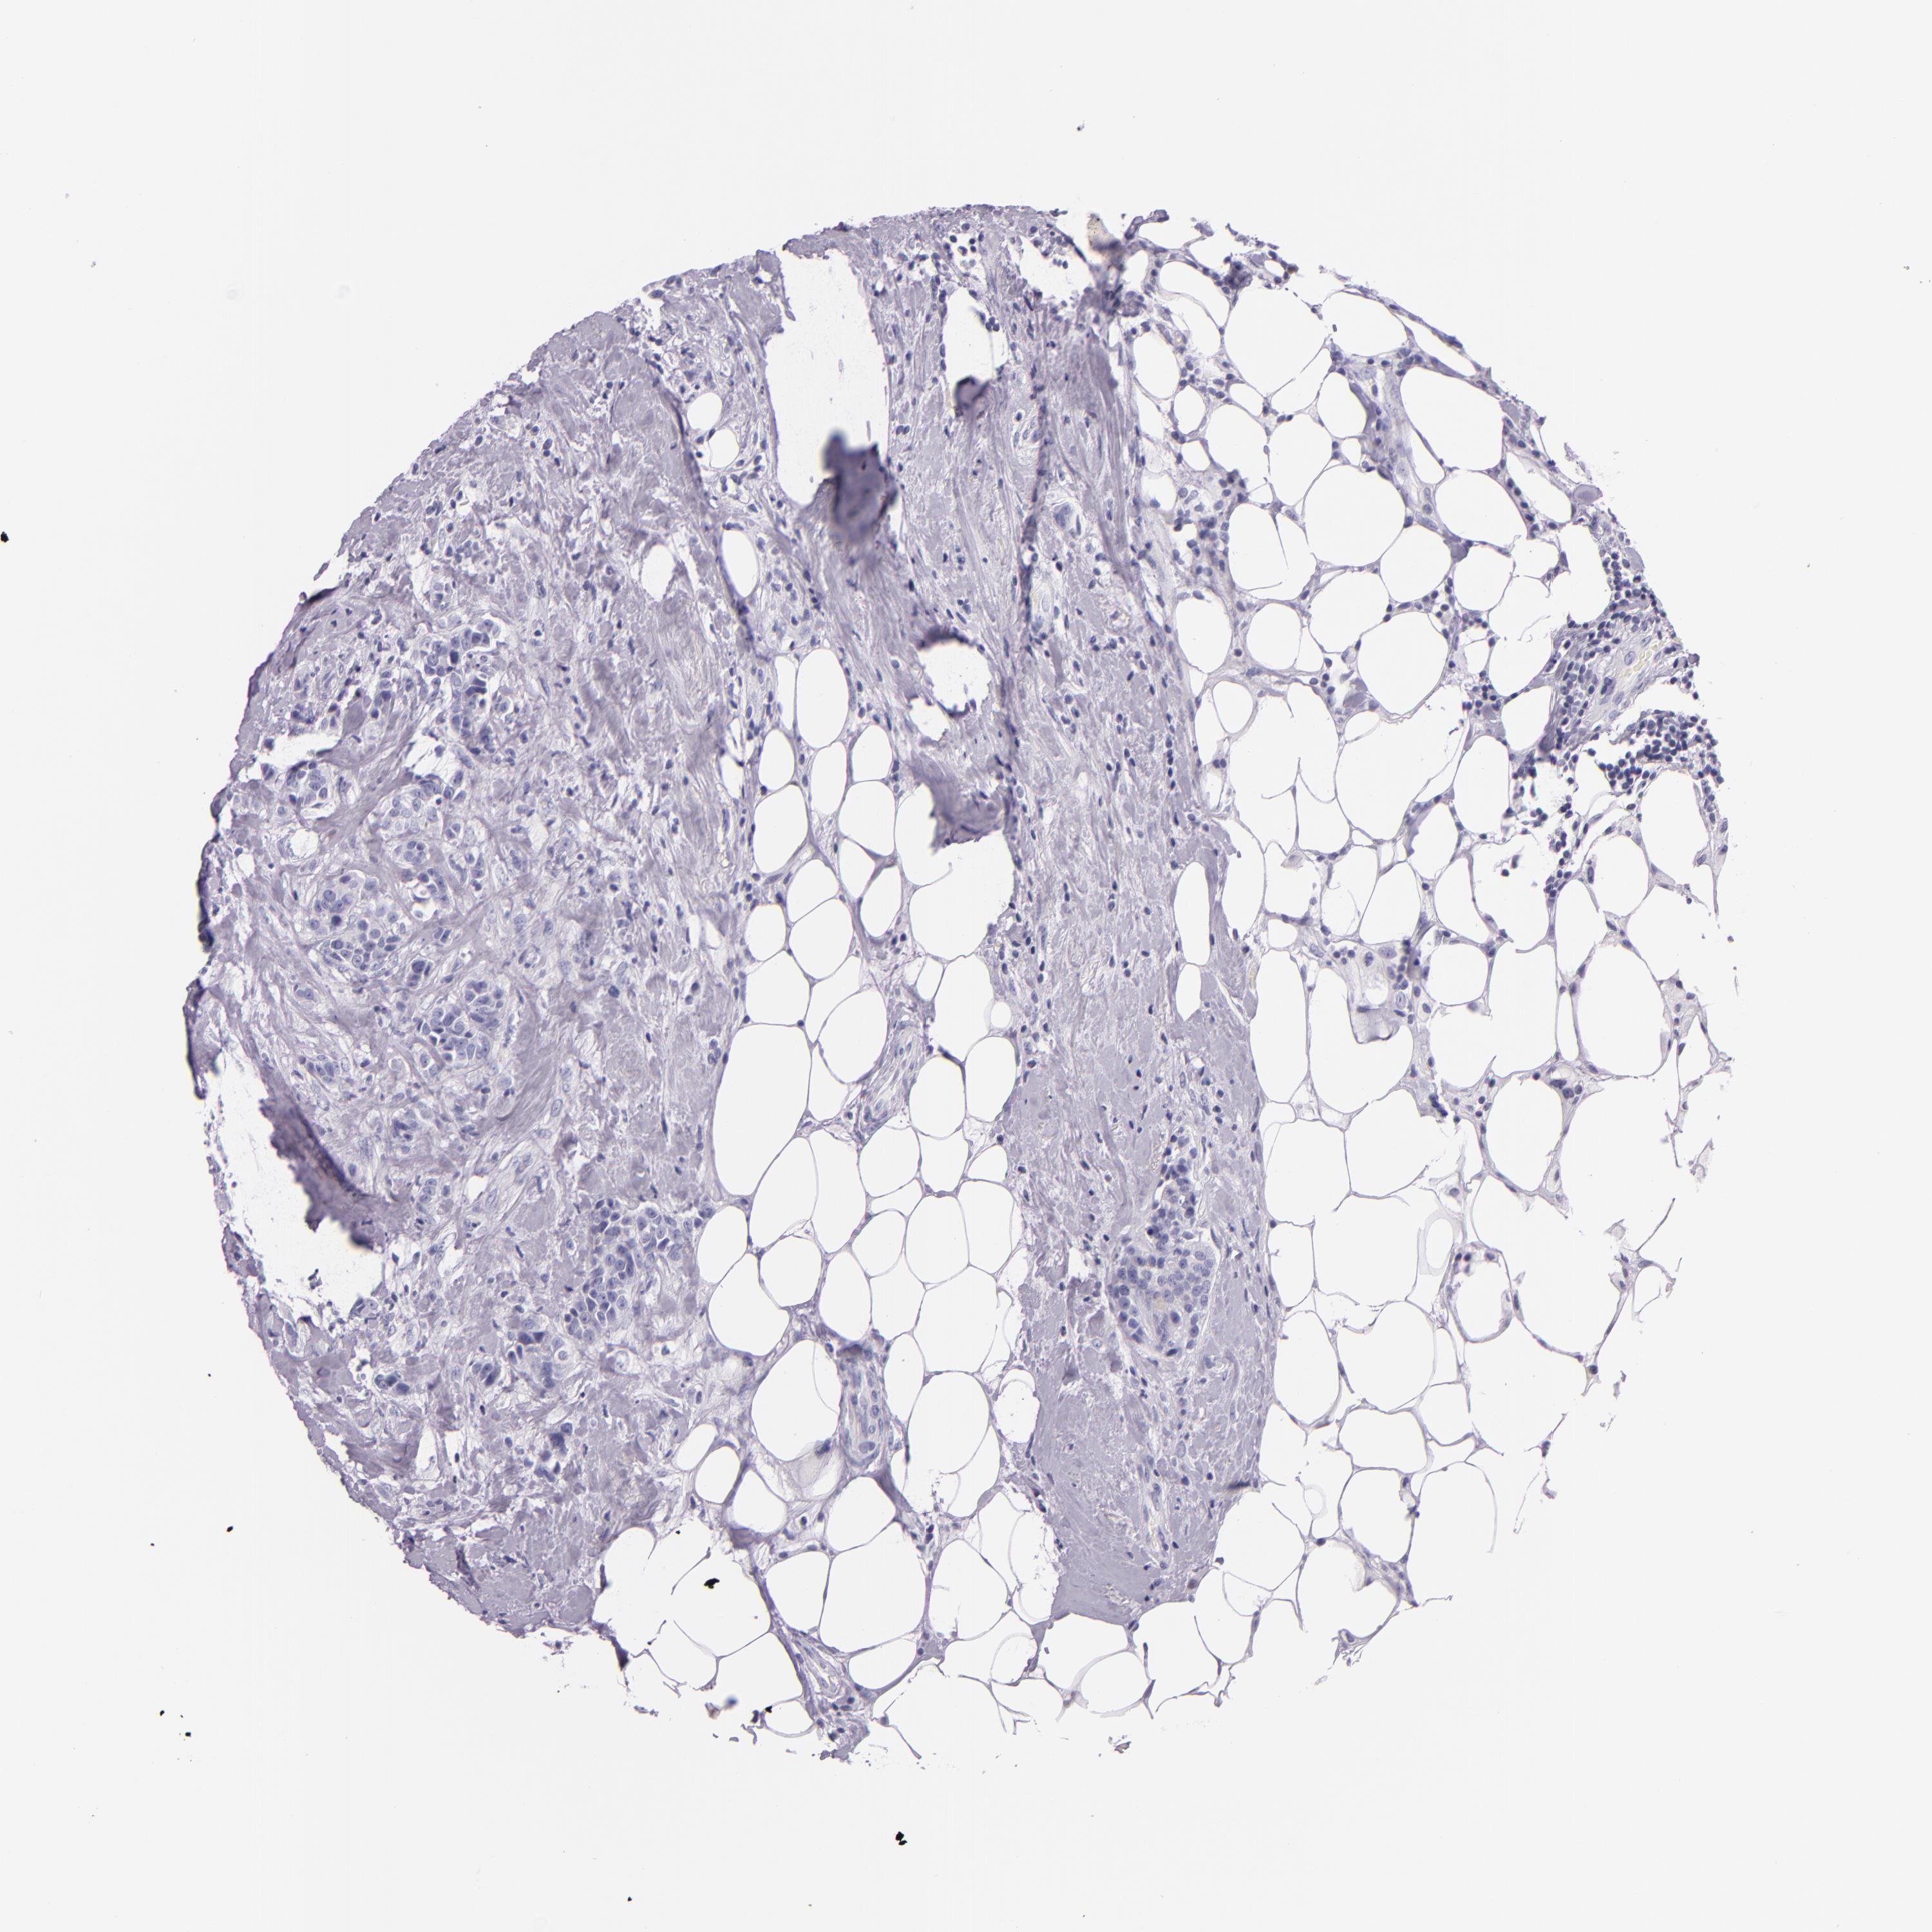

CANCER BREAST CANCER Show tissue menu

Breast cancer

Human cancer